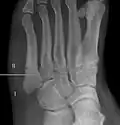

- Proximal diaphysis, typically stress fracture.[12][13]

- Metaphysis: Jones fracture[14]

-Tuberosity: Pseudo-Jones fracture[15] (avulsion fracture).[15]

Normal anatomy:

- Apophysis: Normal at 10 - 16 years.[16]

- Os vesalianum, an accessory bone.[17]

Other proximal fifth metatarsal fractures exist, although they are not as problematic as a Jones fracture. If the fracture enters the intermetatarsal joint, it is a Jones fracture. If, however, it enters the tarsometatarsal joint, then it is likely an avulsion fracture caused by pull from the fibularis brevis tendon. An avulsion fracture at the base of the fifth metatarsal is sometimes called a "dancer's fracture" or a "pseudo Jones fracture", and usually responds readily to non-operative treatment.[18] The X-ray appearance of the developmental "apophysis" in this area may have some resemblance of a fracture, but is not a fracture; it is the secondary ossification center of the metatarsal bone. It is a normal finding that occurs at this site in adolescents.[19] If an injury to that area has occurred, the physician is often able to interpret certain radiographic clues to make the differentiation. An avulsion fracture at this location is typically extra-articular and oriented transversally as compared to the longitudinal orientation of an unfused apophysis.[19]

Zones I and III have been associated with relatively guaranteed union and this union has taken place with only limited restriction of activity combined with early immobilization. On the other hand, zone II has been associated with either delayed or non-union and, consequently, it has been generally agreed that fractures in this area should be considered for some form of internal immobilization, such as internal screw fixation.

These zones can be identified anatomically and on x-ray adding to the clinical usefulness of this classification.[21] Surgical intervention is not, by itself, a guarantee of cure and has its own complication rate. Other reviews of the literature have concluded that conservative, non-operative, treatment is an acceptable option for the non-athlete.[22]

-

Anatomy of the fifth metatarsal. -

3 zone description -

2 zone description